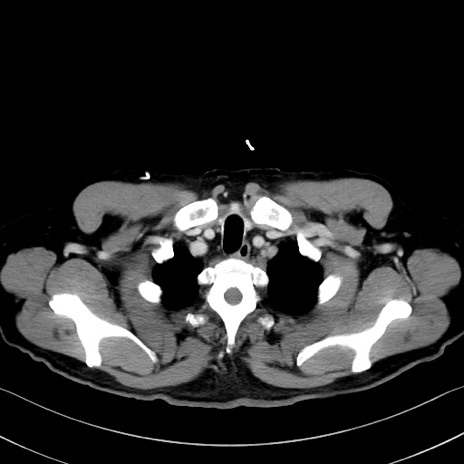

冠状断像

症例35(横断像)

【症例】70歳代 男性

【主訴】腹部膨満、嘔吐

【現病歴】昨日より腹部膨満感出現。本日増悪し、仙痛出現。嘔吐あり、受診。

【既往歴】糖尿病、胆摘後

【身体所見】BP 149/80mmHg、HR 74/min、BT 35.9℃、腹部:膨満、軟、圧痛なし。腸雑音減弱あり。上腹部正中切開瘢痕あり。

【データ】WBC 13500、CRP 1.72